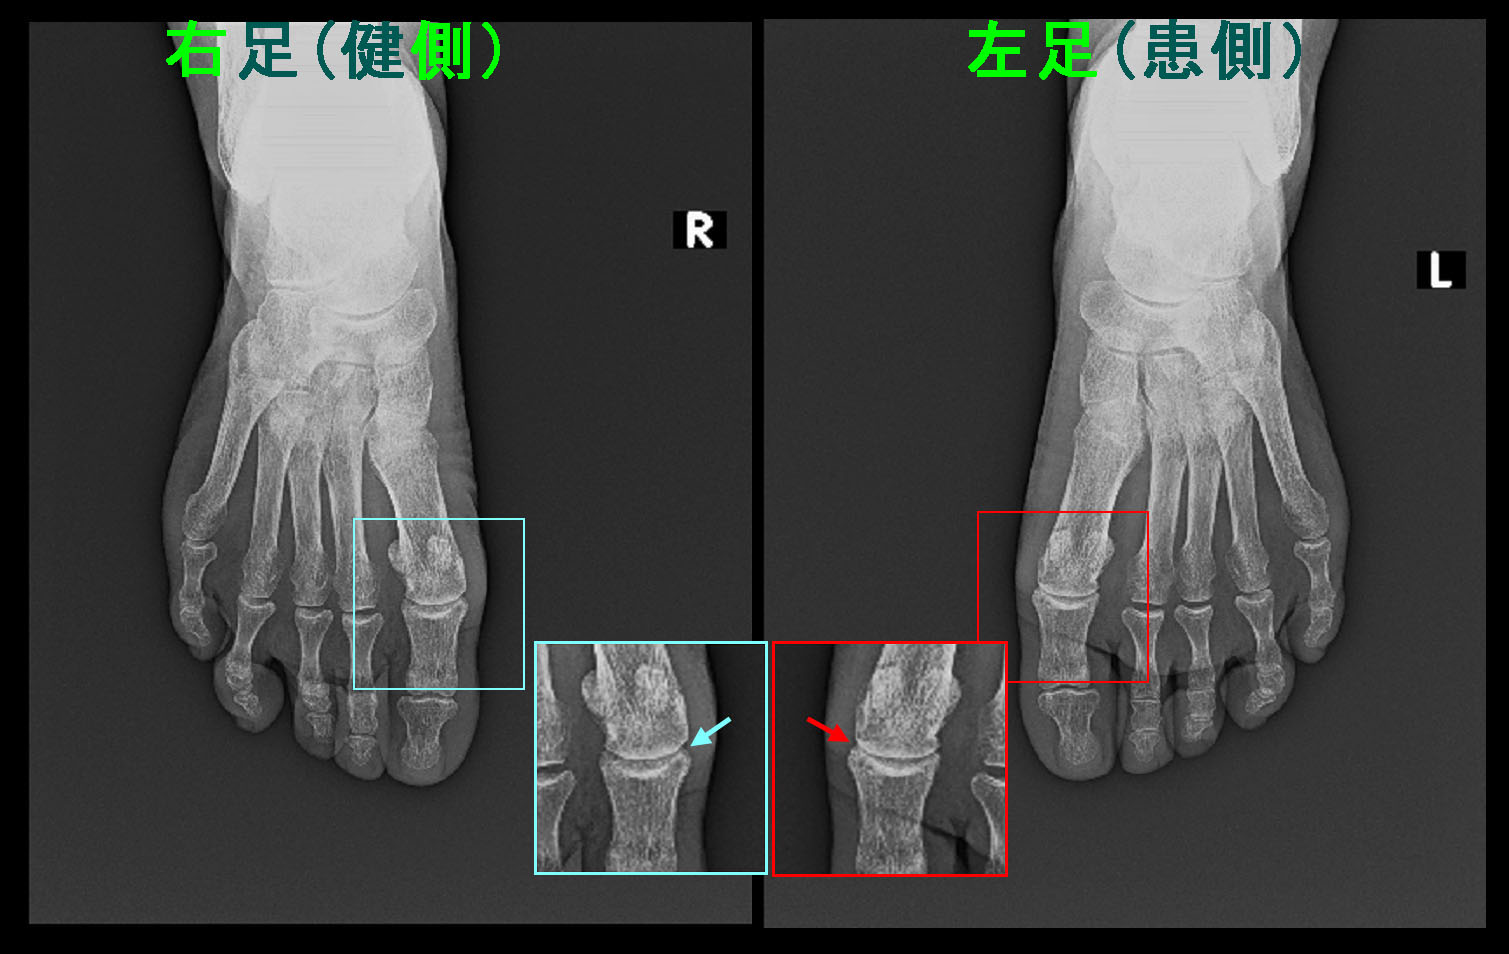

右第1足指MP関節の赤矢印が左第1足指の同部より関節の隙間が幾分狭くなっていて、リウマチによる変形性関節症化の所見と評価されます。

令和6年2月20日には2週間前から左第1足指のMP関節は歩行時VAS5の痛みとなり、同関節が背側位とならないように気を付けて歩いているという訴えとなりました。同日のレントゲン像では令和3年11月(オレンジ矢印)よりさらに関節の隙間は狭くなっていると評価されます(赤矢印)。

67才女RA Xp2.jpg